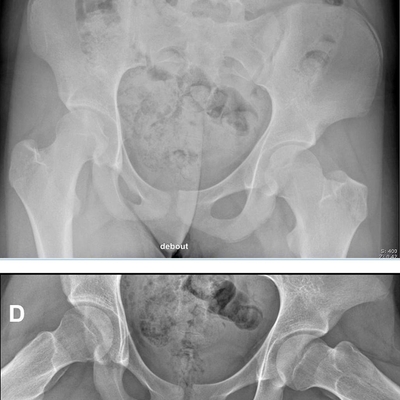

Click on an image below to view more info.